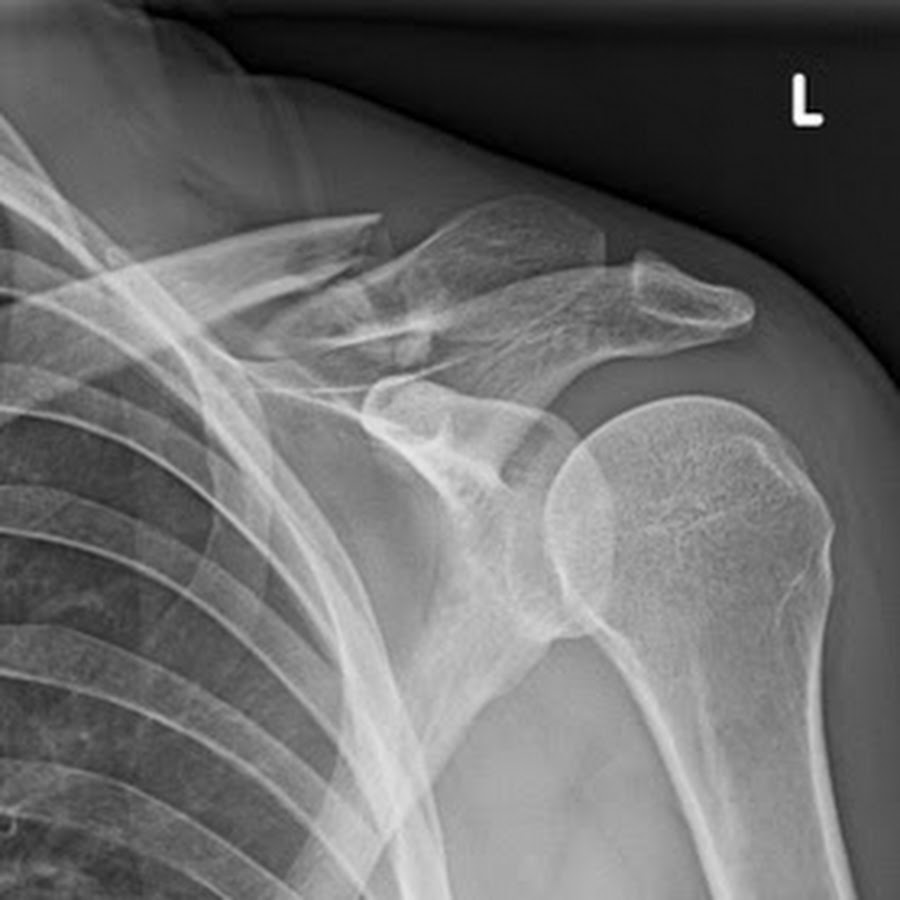

The Role of Imaging in Clavicle Fracture Management

Accurate diagnosis and treatment planning for clavicle fractures rely heavily on imaging studies. Various imaging modalities may be employed, including:

- Plain radiographs (X-rays)

Are X-rays sufficient for diagnosing all clavicle fractures? While plain radiographs are often adequate for initial diagnosis and treatment planning, complex fractures or those with suspected soft tissue involvement may require advanced imaging such as CT or MRI.

Three-dimensional CT reconstructions can be particularly helpful in assessing fracture patterns and planning surgical approaches. How does 3D imaging improve surgical outcomes for clavicle fractures? By providing detailed visualization of the fracture geometry and surrounding anatomy, 3D imaging allows surgeons to optimize implant selection and placement, potentially leading to improved functional outcomes.

Your doctor will X-ray the clavicle to determine if a fracture is present and to determine the most appropriate treatment. Additional tests such as computed tomography (CT) scans or magnetic resonance imaging (MRI) are seldom needed to identify a fracture or determine treatment recommendations.

During the physical exam, your doctor will inspect the affected area for tenderness, swelling, deformity or an open wound. X-rays determine the extent of a broken collarbone, pinpoint its location and determine if there’s injury to the joints. Your doctor might also recommend a CT scan to get more-detailed images.

Thus I don’t manipulate the arm or shoulder as the bones will not stay aligned. X-rays tell me how displaced the fracture is. There is no reason to get additional studies such as a CT scan or MRI unless other injuries are suspected.

During your evaluation with Dr. Hackett in Vail, Colorado, he will examine the fracture and ask you how the injury happened. Generally, there is a visible deformity, or “bump” where the fracture occurred, which makes for a simple diagnosis. He may still order an X-ray to clearly see the precise location and severity of the fracture, and rule out any additional injuries that could have occurred.